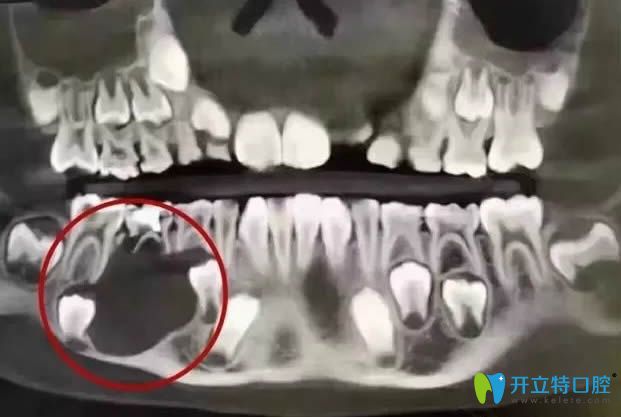

<這就是那位12歲小姑娘的口腔全景CT圖>

被切除下頜骨的口腔全景CT圖

看了這位小姑娘的病例以后,你還會(huì)疑惑乳牙壞了是否會(huì)影響恒牙嗎?你還會(huì)覺(jué)得乳牙齲壞不用補(bǔ),反正是要換新牙的嗎?